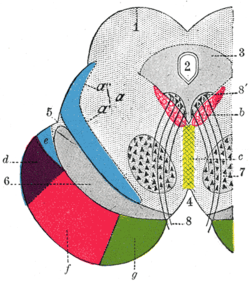

Transverse section through mid-brain. 1. Corpora quadrigemina. 2. Cerebral aqueduct. 3. Central gray stratum. 4. Interpeduncular space. 5. Sulcus lateralis. 6. Substantia nigra. 7. Red nucleus of tegmentum. 8. Oculomotor nerve, with 8’, its nucleus of origin. a. Lemniscus (in blue) with a’ the medial lemniscus and a" the lateral lemniscus. b. Medial longitudinal fasciculus. c. Raphé. d. Temporopontine fibers. e. Portion of medial lemniscus, which runs to the lentiform nucleus and insula. f. Cerebrospinal fibers. g. Frontopontine fibers. | |